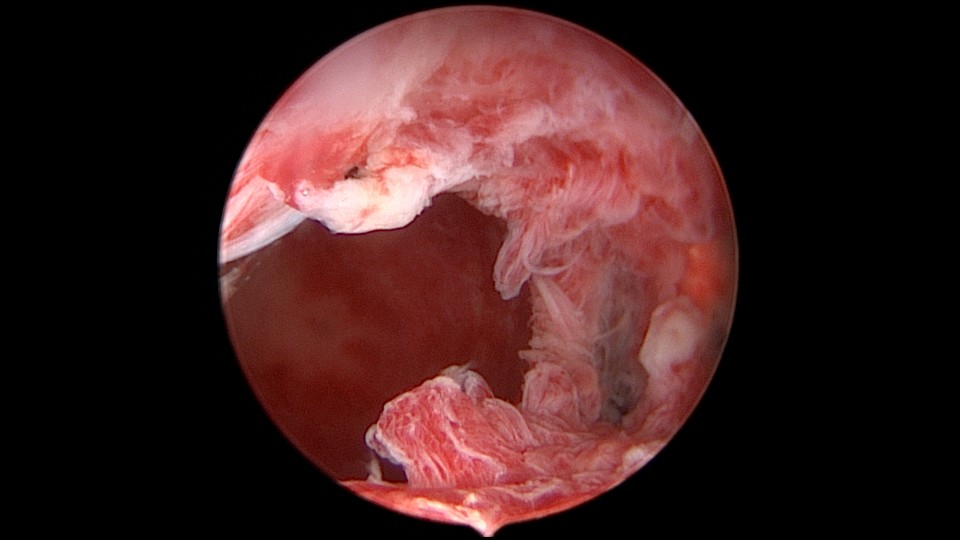

患者56岁,G3P1,顺产1次。安环20+年,绝经10年,下腹坠胀不适1周,B超提示子宫后位,宫内无回声区2.4cm×1.5cm。宫颈外口见节育环尾丝,环纵臂卡在宫颈管内,宫腔镜难以进入宫腔,取环后看到宫腔粘稠白色脓液,宫腔左侧前后壁粘连,膨宫液冲洗脓液,宫腔无其他异常。